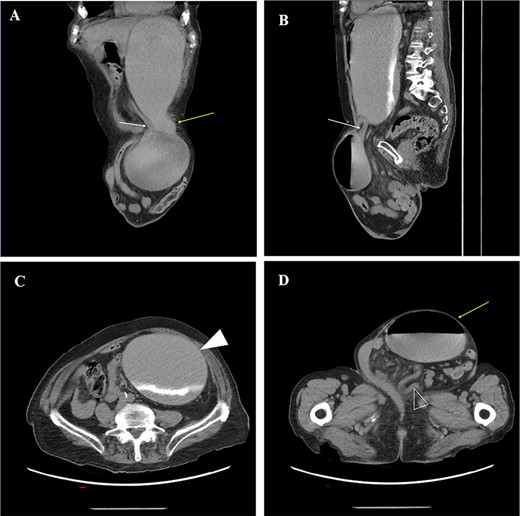

A 93-year-old man presented to the emergency department complaining of intractable non-bloody, non-bilious emesis. He reported a 25-year history of a progressively enlarging left inguinoscrotal hernia associated with intermittent pain, discomfort and early satiety. Two weeks previously he had presented to the emergency department (ED) with similar symptoms but left after receiving fluids and spontaneous resolution. Physical examination revealed a massive, incarcerated left inguinal hernia which obscured the penis, focal tenderness at the hernia and no signs of peritonitis or strangulation. Computed tomography (CT) revealed a left inguinal hernia that contained loops of small bowel (Fig. 1D), and a portion of the gastric body and antrum with severe proximal dilation of the stomach (Fig. 1A), concerning for GOO. An NG tube was placed with immediate evacuation of 2L of contents. The patient noted instant relief as well as improved pain at the hernia site.

(A) oblique coronal reconstructions from a non-contrast CT demonstrates the gastric body (yellow arrow) entering the left inguinal hernia, and the obstructed gastric antrum (white arrow) exiting the hernia; (B) oblique sagittal reconstruction from a CT demonstrates the obstructed gastric antrum (white arrow); (C) axial non-contrast CT through the abdomen demonstrates a dilated gastric body and fundus (white arrowhead) with layering contrast fluid and ingested material; (D) axial non-contrast CT image through the pelvis demonstrates a large left inguinal hernia containing the obstructed gastric body (yellow arrow) and multiple loops of decompressed small bowel (open arrowhead).